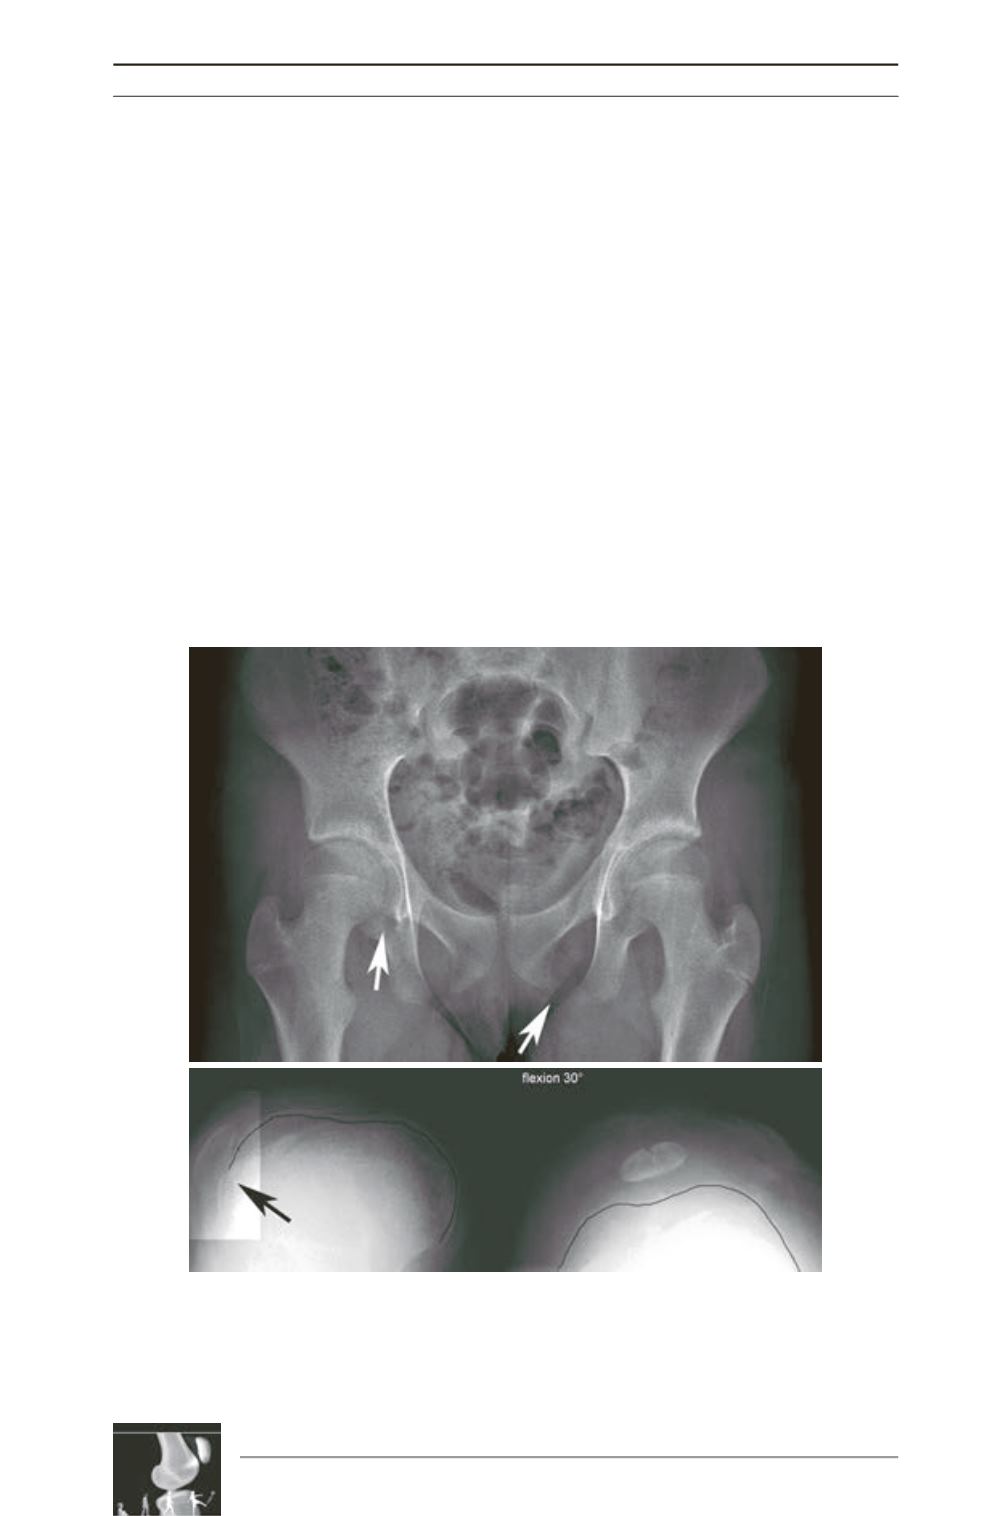

2) Small patella syndrome

(SPS) also called

ischiopatellar dysplasia, coxopodo patellar

syndrome, or Scott-Taor syndrome, is a rare

autosomal dominant disorder. This bone

dysplasia is characterized by patellar a/

hypoplasia and pelvic anomalies, including

bilateral absent or delayed ossification of the

ischiopubic junction and infra-acetabular

axe cut notches

(fig. 5). Other major signs are a

wide gap between the first and second toes,

short fourth and fifth rays of the feet, and pes

planus. Various other skeletal anomalies have

been reported, such as elongated femoral necks,

flattened and widened proximal femoral

epiphyses, hypoplasia of the lesser trochanter,

and tarsal anomalies. At contrary to NPS, no

nails change, iliac horn, elbow anomaly, or renal

disease is associated with this condition [3].

Fig. 5: Small patella syndrome (SPS): pelvic anomalies on AP X-ray, including bilateral

absent ossification of the ischiopubic junction (arrow), infra-acetabular axe cut

notches (arrow) and elongated femoral necks (up). Permanent patellar dislocation on

the left side not yet treated, right side had been reduced surgically after lateral

release, Judet quadriceps desinsertion, Grammont procedure, MPFL reconstruction

and patelloplasty… (down).